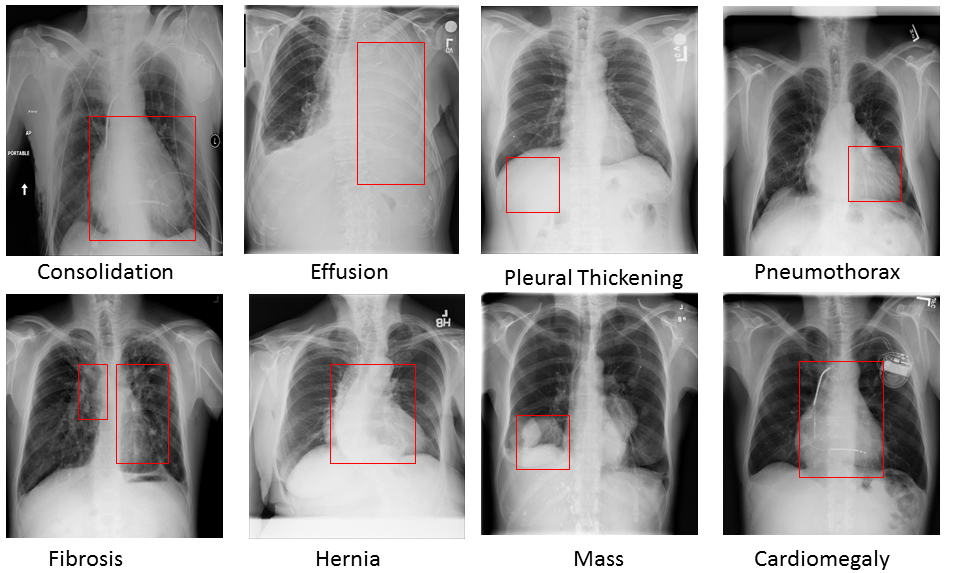

Pulmonary diseases can cause severe respiratory problems, leading to sudden death if not treated timely. Many researchers have utilized deep learning systems to diagnose pulmonary disorders using chest X-rays (CXRs). However, such systems require exhaustive training efforts on large-scale data to effectively diagnose chest abnormalities. Furthermore, procuring such large-scale data is often infeasible and impractical, especially for rare diseases. With the recent advances in incremental learning, researchers have periodically tuned deep neural networks to learn different classification tasks with few training examples. Although, such systems can resist catastrophic forgetting, they treat the knowledge representations independently of each other, and this limits their classification performance. Also, to the best of our knowledge, there is no incremental learning-driven image diagnostic framework that is specifically designed to screen pulmonary disorders from the CXRs. To address this, we present a novel framework that can learn to screen different chest abnormalities incrementally. In addition to this, the proposed framework is penalized through an incremental learning loss function that infers Bayesian theory to recognize structural and semantic inter-dependencies between incrementally learned knowledge representations to diagnose the pulmonary diseases effectively, regardless of the scanner specifications. We tested the proposed framework on five public CXR datasets containing different chest abnormalities, where it outperformed various state-of-the-art system through various metrics.